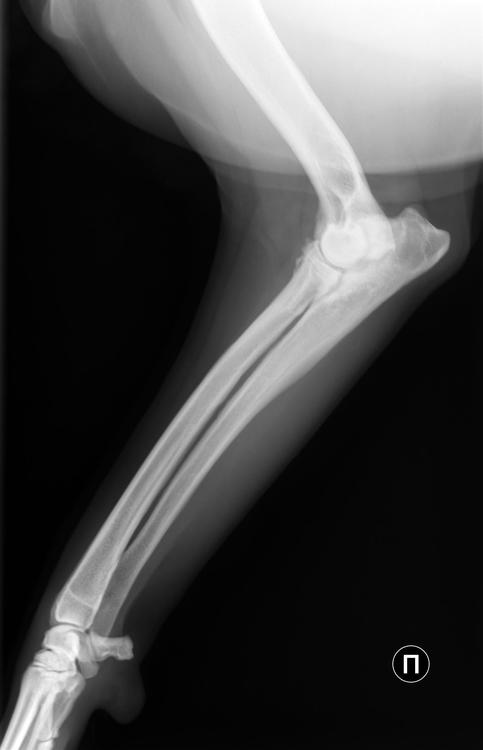

Бэкки Опубликовано 19 апреля, 2019 Опубликовано 19 апреля, 2019 Добрый день! Съездили вчера с Дусенькой к доктору, при осмотре доктор сказал, что до конца не сгибаются локтевые суставы, тазобедренные вопросов не вызвали, сделали рентген локтевых суставов и поясничного отдела. Результаты ниже. Снимки записаны на диск, но у меня нет дисковода)) Муж сможет днем на работе открыть и переслать мне, если нужны. Рекомендовано худеть и худеть на много, до 30 кг, а сейчас Дусенька 35,5 кг. , противовоспалительное пока не назначил, считает, что снижение веса значительно облегчит состояние, а пить лекарства еще успеем. Так что, будем много плавать, это нам можно, и мало кушать) 1 5